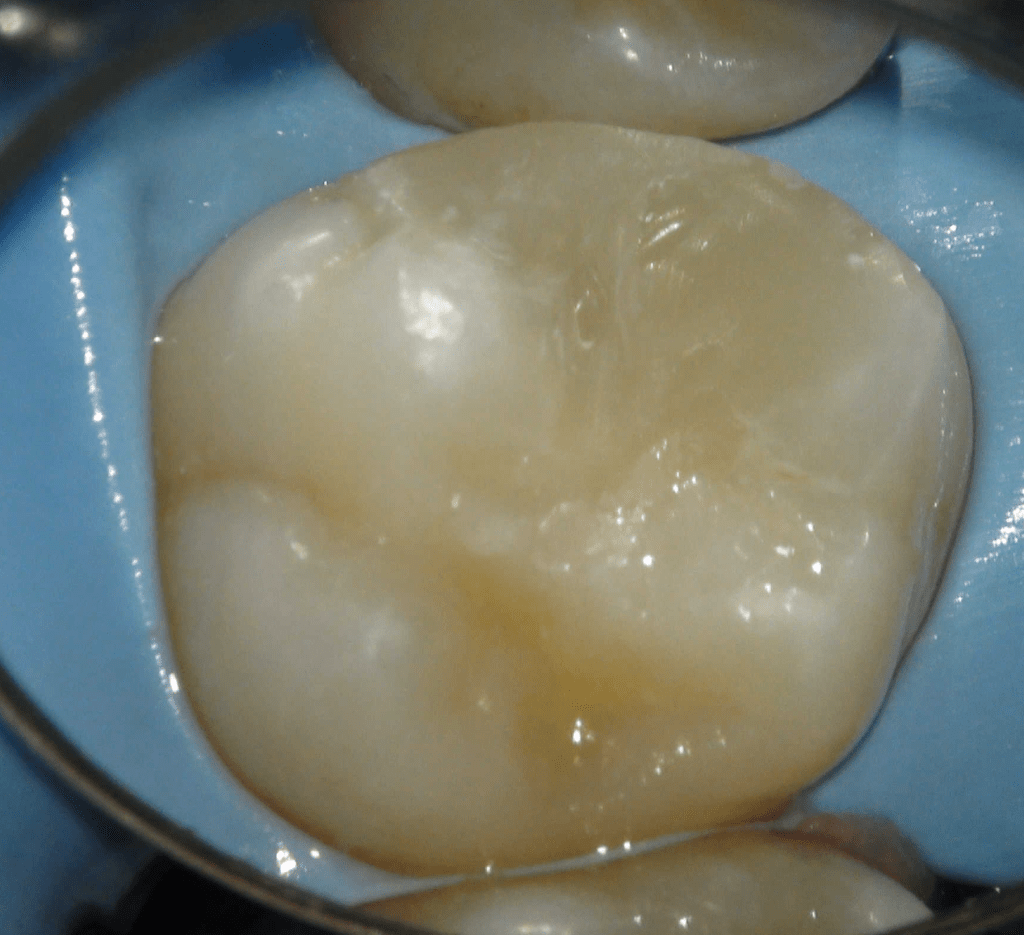

Pulpotomía biodentine + reco preendio